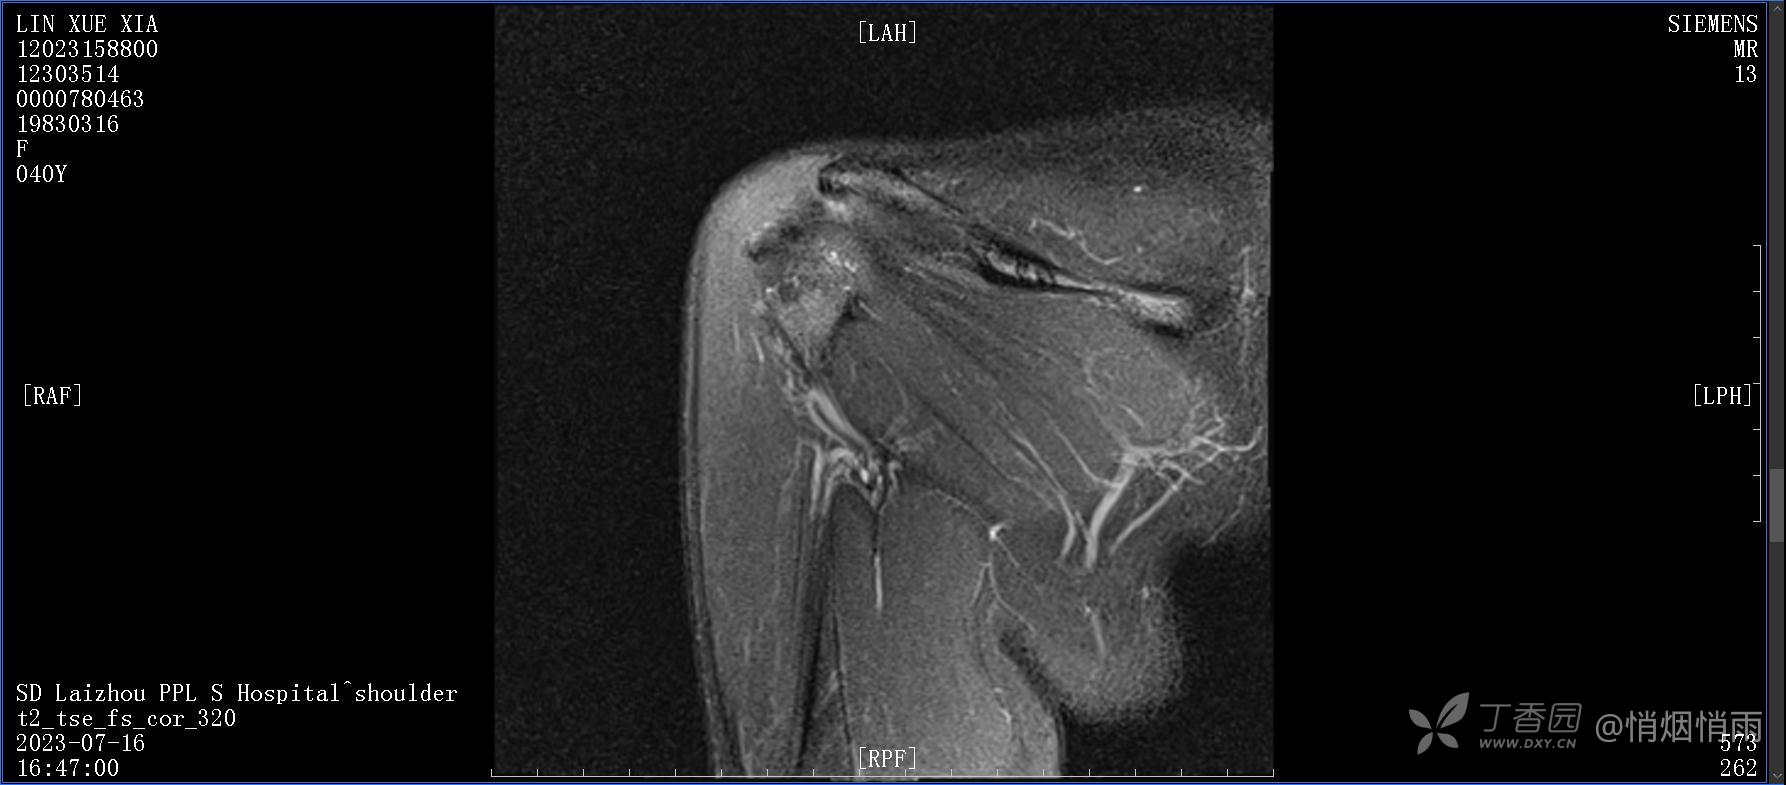

查体:右肩关节局部轻度肿胀,肩胛区压痛明显,痛处不固定,肩关节痛性活动受限,jobe test(+),lift -off test(+),中指、环指感觉较余指减退,余肢端感觉及血运情况可。

目前的诊断,暂时依据辅助检查诊为肩袖损伤,但是患者疼痛的性质和特点,却不是单纯的肩袖损伤所致。考虑过胸廓出口综合征,但是该疾病会出现肩胛区的疼痛吗?(由于考虑到费用的问题,没再进行下一步的检查)带状疱疹会有如此的症状吗?